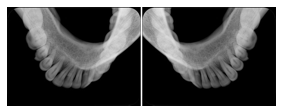

2 Occlusal Vertical Maxilla A Dental Image Layout

DL-C001A

Reference: DL-C001-U1L0

Reference: DL-C001-U2L0

2 Occlusal Vertical Mandible A Dental Image Layout

DL-C002A

Reference: DL-C002-U0L1

Reference: DL-C002A-U0L2